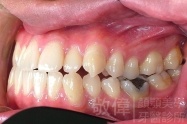

變臉矯正,原來戽斗妹跟大歪臉變成自信正妹

經由本院3D數影X光影像儀分析、與3D齒顎顏矯正技術,再配合口腔顎面正顎專科醫師施以正顎手術治療,雙方共同合作,使患者臉部外觀有很好的改善,大歪變小歪,產生了天南地北的大改變,她的人生也整個變得不一樣。

因為矯正與正顎手術的配合,使「戽斗妹」變成了「陽光正妹」,完全的改變了她的人生,在面對各種場合、與人交際都散發出自信微笑。所以,奉勸家長,如果小朋友有臉顎畸型的問題,應該考慮配合做這種簡單、安全、有效的正顎手術。